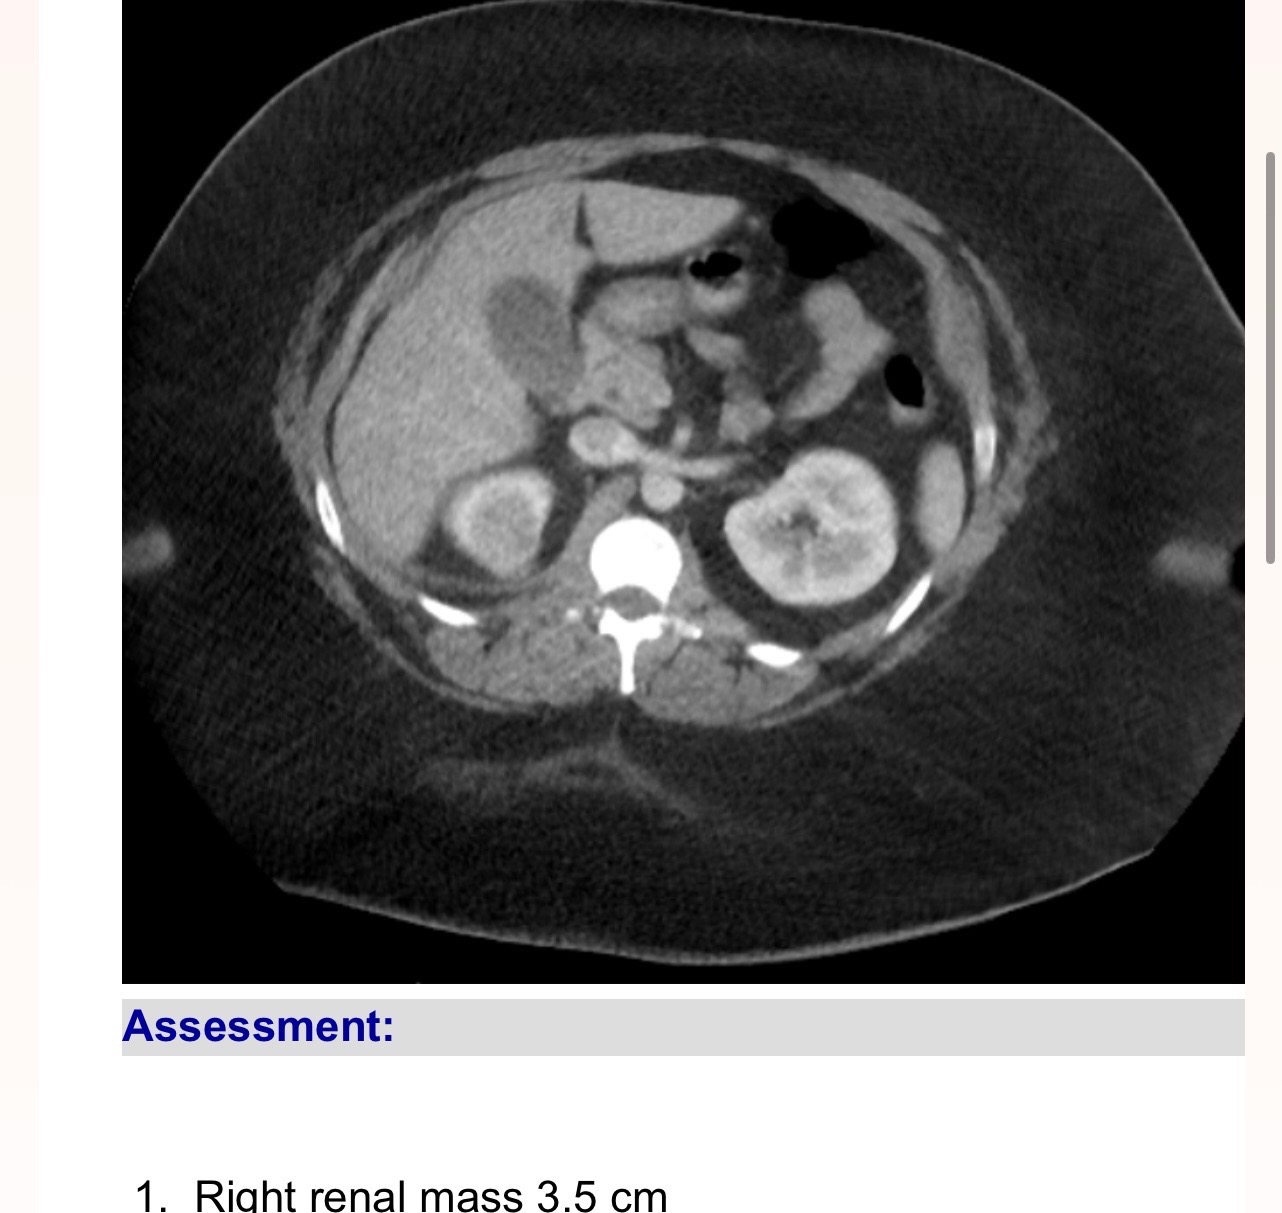

My daughter is facing one of the most difficult times of her life. She was recently diagnosed with Renal Cell Carcinoma, a form of kidney cancer, and just as we were coming to terms with this devastating news, she lost her job and her medical insurance. The doctors have told us that she needs life-saving surgery in just two weeks, but without insurance, the costs are overwhelming.

Because her job ended after her diagnosis, she no longer has medical coverage and must pay for COBRA insurance out of pocket to receive the surgery and follow-up care she desperately needs. The surgery will remove the masses and, hopefully, the cancer located in them. The financial burden is immense, and the stress of figuring out how to pay for everything is taking a toll on her health and our family.